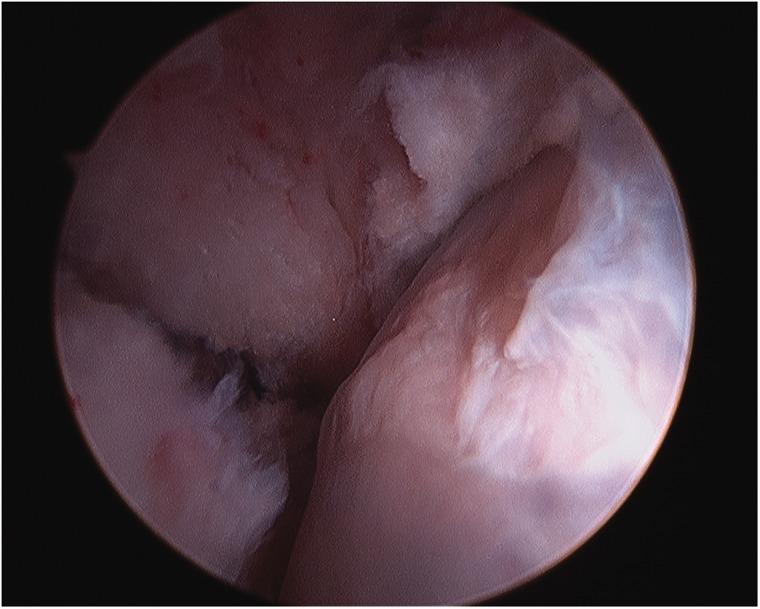

Arthroscopy of the pediatric hip began in 1977 with a publication by Gross. Interest was relatively slow to develop in the 1980s and 1990s. Coupled with the success of hip arthroscopy in the adult, interest heightened in applying the procedure to a variety of pediatric hip disorders, given that the alternative was an open surgical hip dislocation. The success of this initial group of pediatric hip arthroscopist's has further expanded the application of hip arthroscopy as the primary or adjunct procedure for the management of intra-articular problems of the pediatric hip.

小儿髋关节镜检查始于1977年格罗斯发表的一篇文章。在20世纪80年代和90年代,其发展相对缓慢。鉴于成人髋关节镜手术的成功,加上替代方案是开放性髋关节脱位手术,人们对将该手术应用于各种小儿髋关节疾病的兴趣日益浓厚。首批小儿髋关节镜医生取得的成功进一步扩大了髋关节镜检查作为治疗小儿髋关节关节内问题的主要或辅助手术的应用范围。